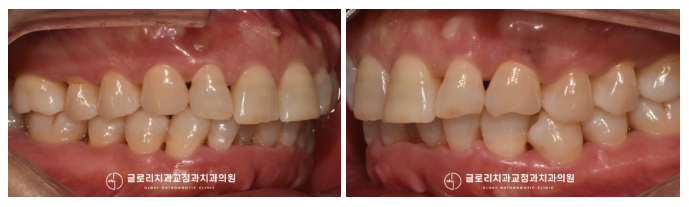

실제 구강 사진을 확인해 보니

안쪽으로 배열되어 있는

하악 전치부 일부 치아를 볼 수 있었습니다.

하악에 비해 상악은 돌출되어 있는 듯한

느낌을 주고 있었는데요.

안으로 들어가 있던 하악 치아가

올곧게 자리를 잡아 고르게 배열되어 있는데요.

이때 벌어진 틈새를 메꾸기 위해

레진 수복도 함께 도와드렸더니

심미성이 배가 되어 훨씬 건강한 모습으로

바뀐 것을 볼 수 있었습니다.